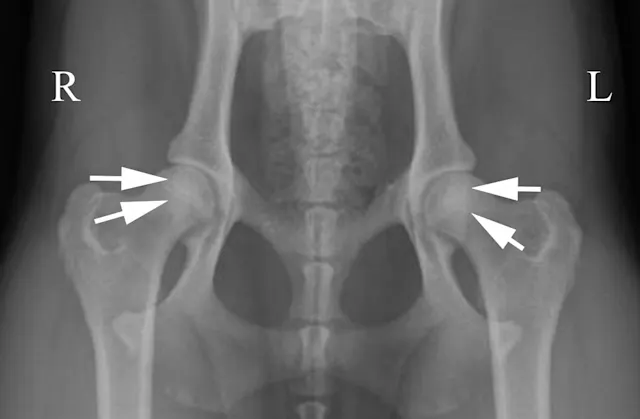

A radiograph displays a dog's pelvis, with clear indications of the left and right sides labeled. Arrows point to the hip joints, highlighting signs of hip dysplasia, characterized by abnormal joint spacing and alignment.

Oblique positioning will result in false assessment of dorsal acetabular rim coverage of the femoral head, as shown in Figure 2C. The dorsal acetabular rim (white arrows) appears to provide more coverage of the right femoral head and less coverage on the left side. When the patient is properly positioned, as in Figure 2D, it is evident that coverage of the dorsal acetabular rim (white arrows) is similar on both sides.